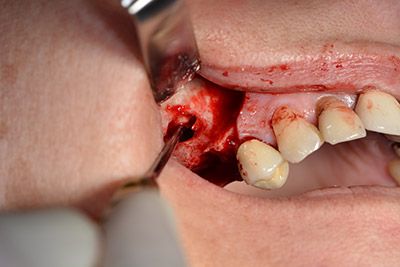

The next step was the sinus floor elevation with simultaneous implantation. The Implantmed also had a presetting at the first position for the buccal fenestration of the maxillary sinus wall.

The fenestration was prepared at 35,000 rpm and then the nasal mucosa were prepared in the cranial direction (Fig. 13 to 14).

preparation of the nasal mucosa

Image 13

Inclined drilling

Image 14